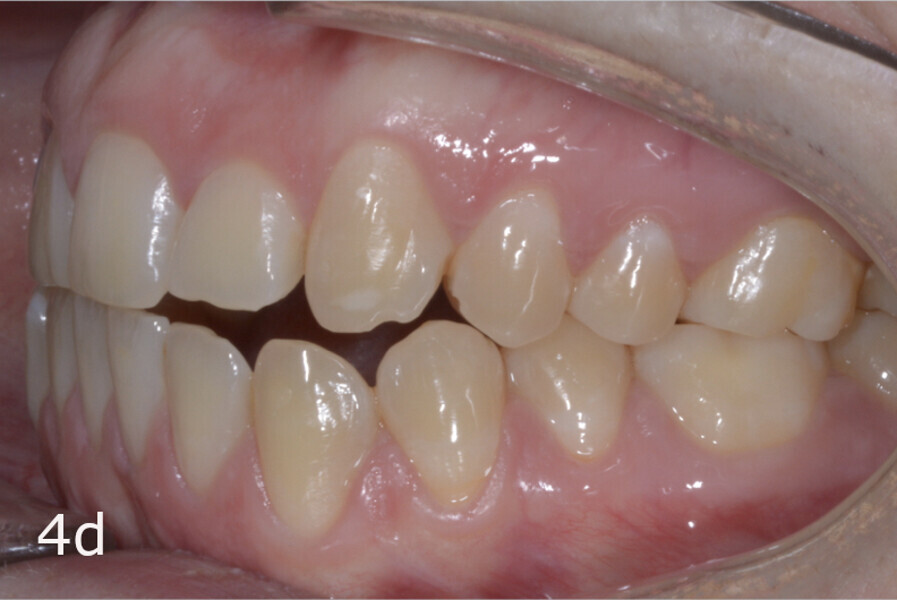

The 23-year-old dolichofacial female patient complained of not being able to chew properly. Facial examination showed a convex profile, an enlarged lower facial height, and a skeletal Class III malocclusion (Figs. 1–3). Intra-oral examination revealed an Angle Class III right subdivision malocclusion, anterior open bite, no overjet and a maxillary dental midline deviated about 3 mm to the right compared with the mandibular dental midline (Fig. 4). The panoramic radiograph confirmed previous extraction of the maxillary right first premolar and the presence of all four third molars (Figs. 5 & 6).

The treatment objectives included closing the anterior open bite, achieving a bilateral Angle Class I relationship and a proper overjet and overbite, correcting the midline discrepancies, and achieving a profile harmonisation. The treatment plan consisted of orthodontic camouflage treatment with asymmetric distalisation in three of the four quadrants using Invisalign aligners (Align Technology) and third molar extraction. The Invisalign Comprehensive package was chosen, and 63 pairs of aligners were used (Figs. 7–10). Each aligner was worn for 20 hours a day for one week each. The use of Class III elastics on both sides was indicated. Afterwards, ten refinement aligners were needed to improve the interdigitation on the right side (Figs. 11 & 12).

The total treatment time was 15 months. An Angle Class I relationship was established along with adequate anterior and canine guidance, establishing a functional occlusion. This not only ensures optimal masticatory function but also protects the teeth and the temporomandibular joint from excessive force. Maxillary and mandibular fixed retention were installed at the end of the treatment (Figs. 13–19).